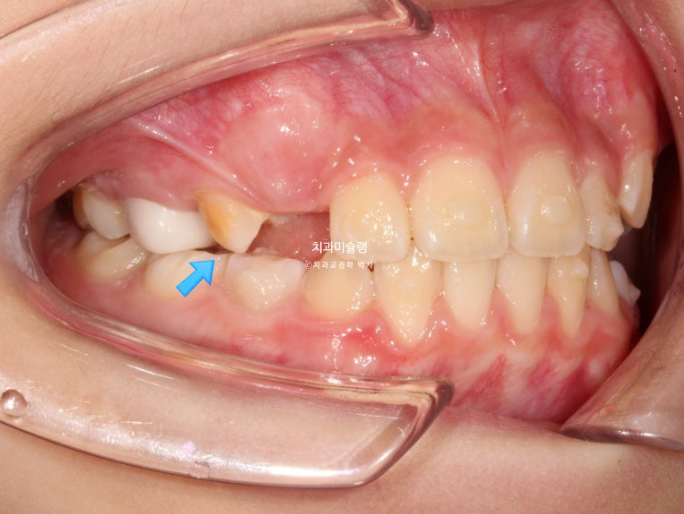

24.02

파란 화살표의 튀어나온 부분을 wing 이라고 부릅니다.

날개같이 생겼기 때문입니다.

위, 아래 장치에 총 4개의 Wing이 불어 나오며 이 Wing 때문에 아래턱을 내밀어 무는 위치로 유도가 됩니다.

근기능장치의 원리는 쉽게 말해 정상 위치에 턱이 적응하게 함으로써 실제로 아래턱뼈가 자라게 해주는 것 이라고 할 수 있겠습니다.